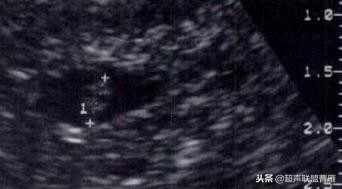

有的图像卵黄囊YS只是两条平行的细短线